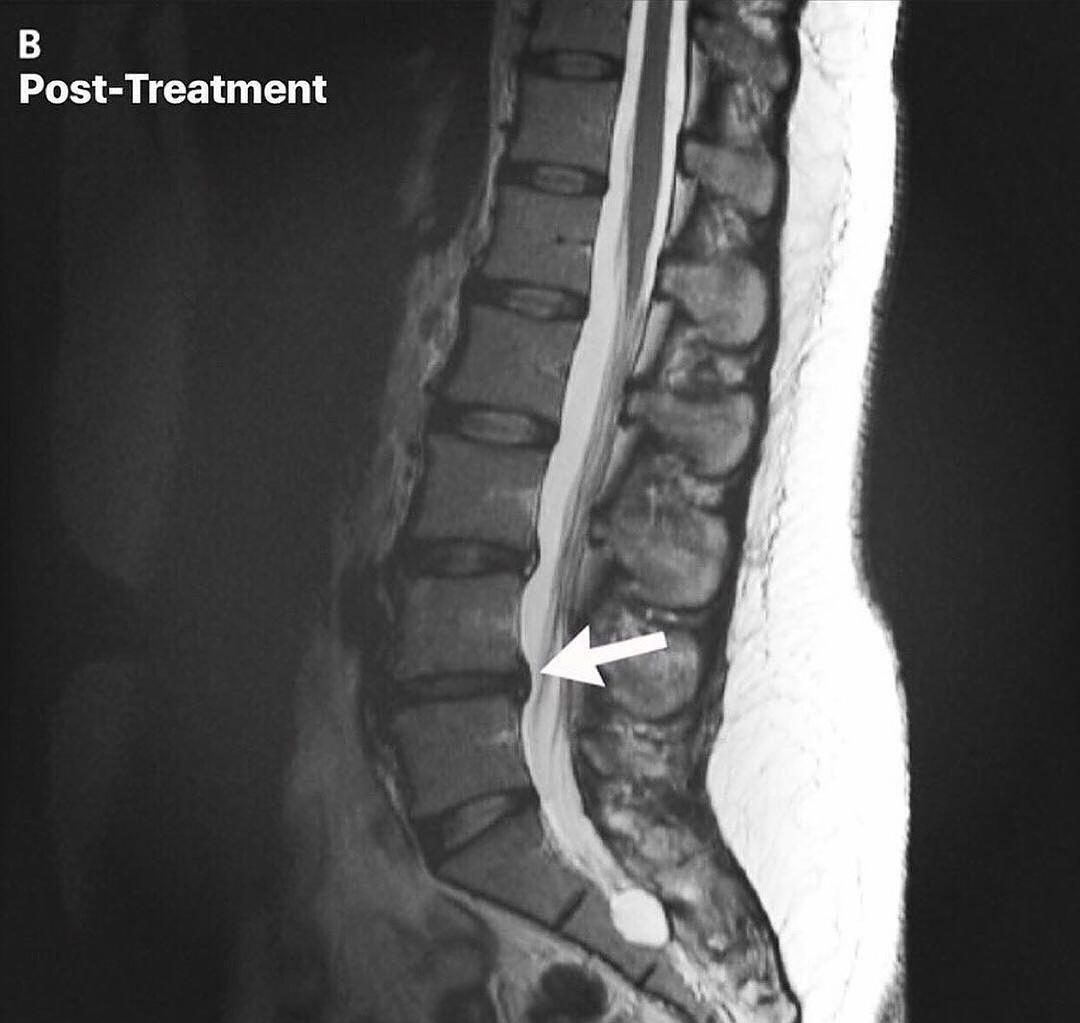

Spinal Disc Rehabilitation in Inver Grove Heights

Advanced care for disc injuries, herniations, and chronic spinal conditions

Spinal disc injuries require more than symptom-based care. Our spinal disc rehabilitation approach in Inver Grove Heights focuses on restoring movement, reducing pressure on the disc, and improving how the spine and nervous system work together over time. Care is guided by imaging, clinical findings, and measured progress, not guesswork or force.This care is designed for people dealing with disc herniations, disc bulges, sciatica, chronic back or neck pain, and those who have not improved with traditional chiropractic care. It is also appropriate for individuals looking for non surgical disc care before considering injections or surgery.